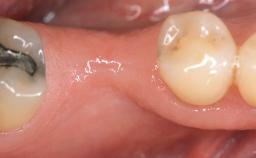

A 30-year-old woman was referred by her general dentist for evaluation of an esthetic complication related to previous implant treatment for congenitally missing maxillary lateral incisors. The patient’s chief complaint was the inadequate esthetic appearance of her smile. The case demonstrates the use of a combined approach to achieve optimal results. Two different flap designs - a tunnel technique and a coronally advanced flap - are employed based on the surgical objectives for the affected site.

Soft Tissue Anatomy Intact Defective

Soft Tissue Contour and Volume Slightly compromised